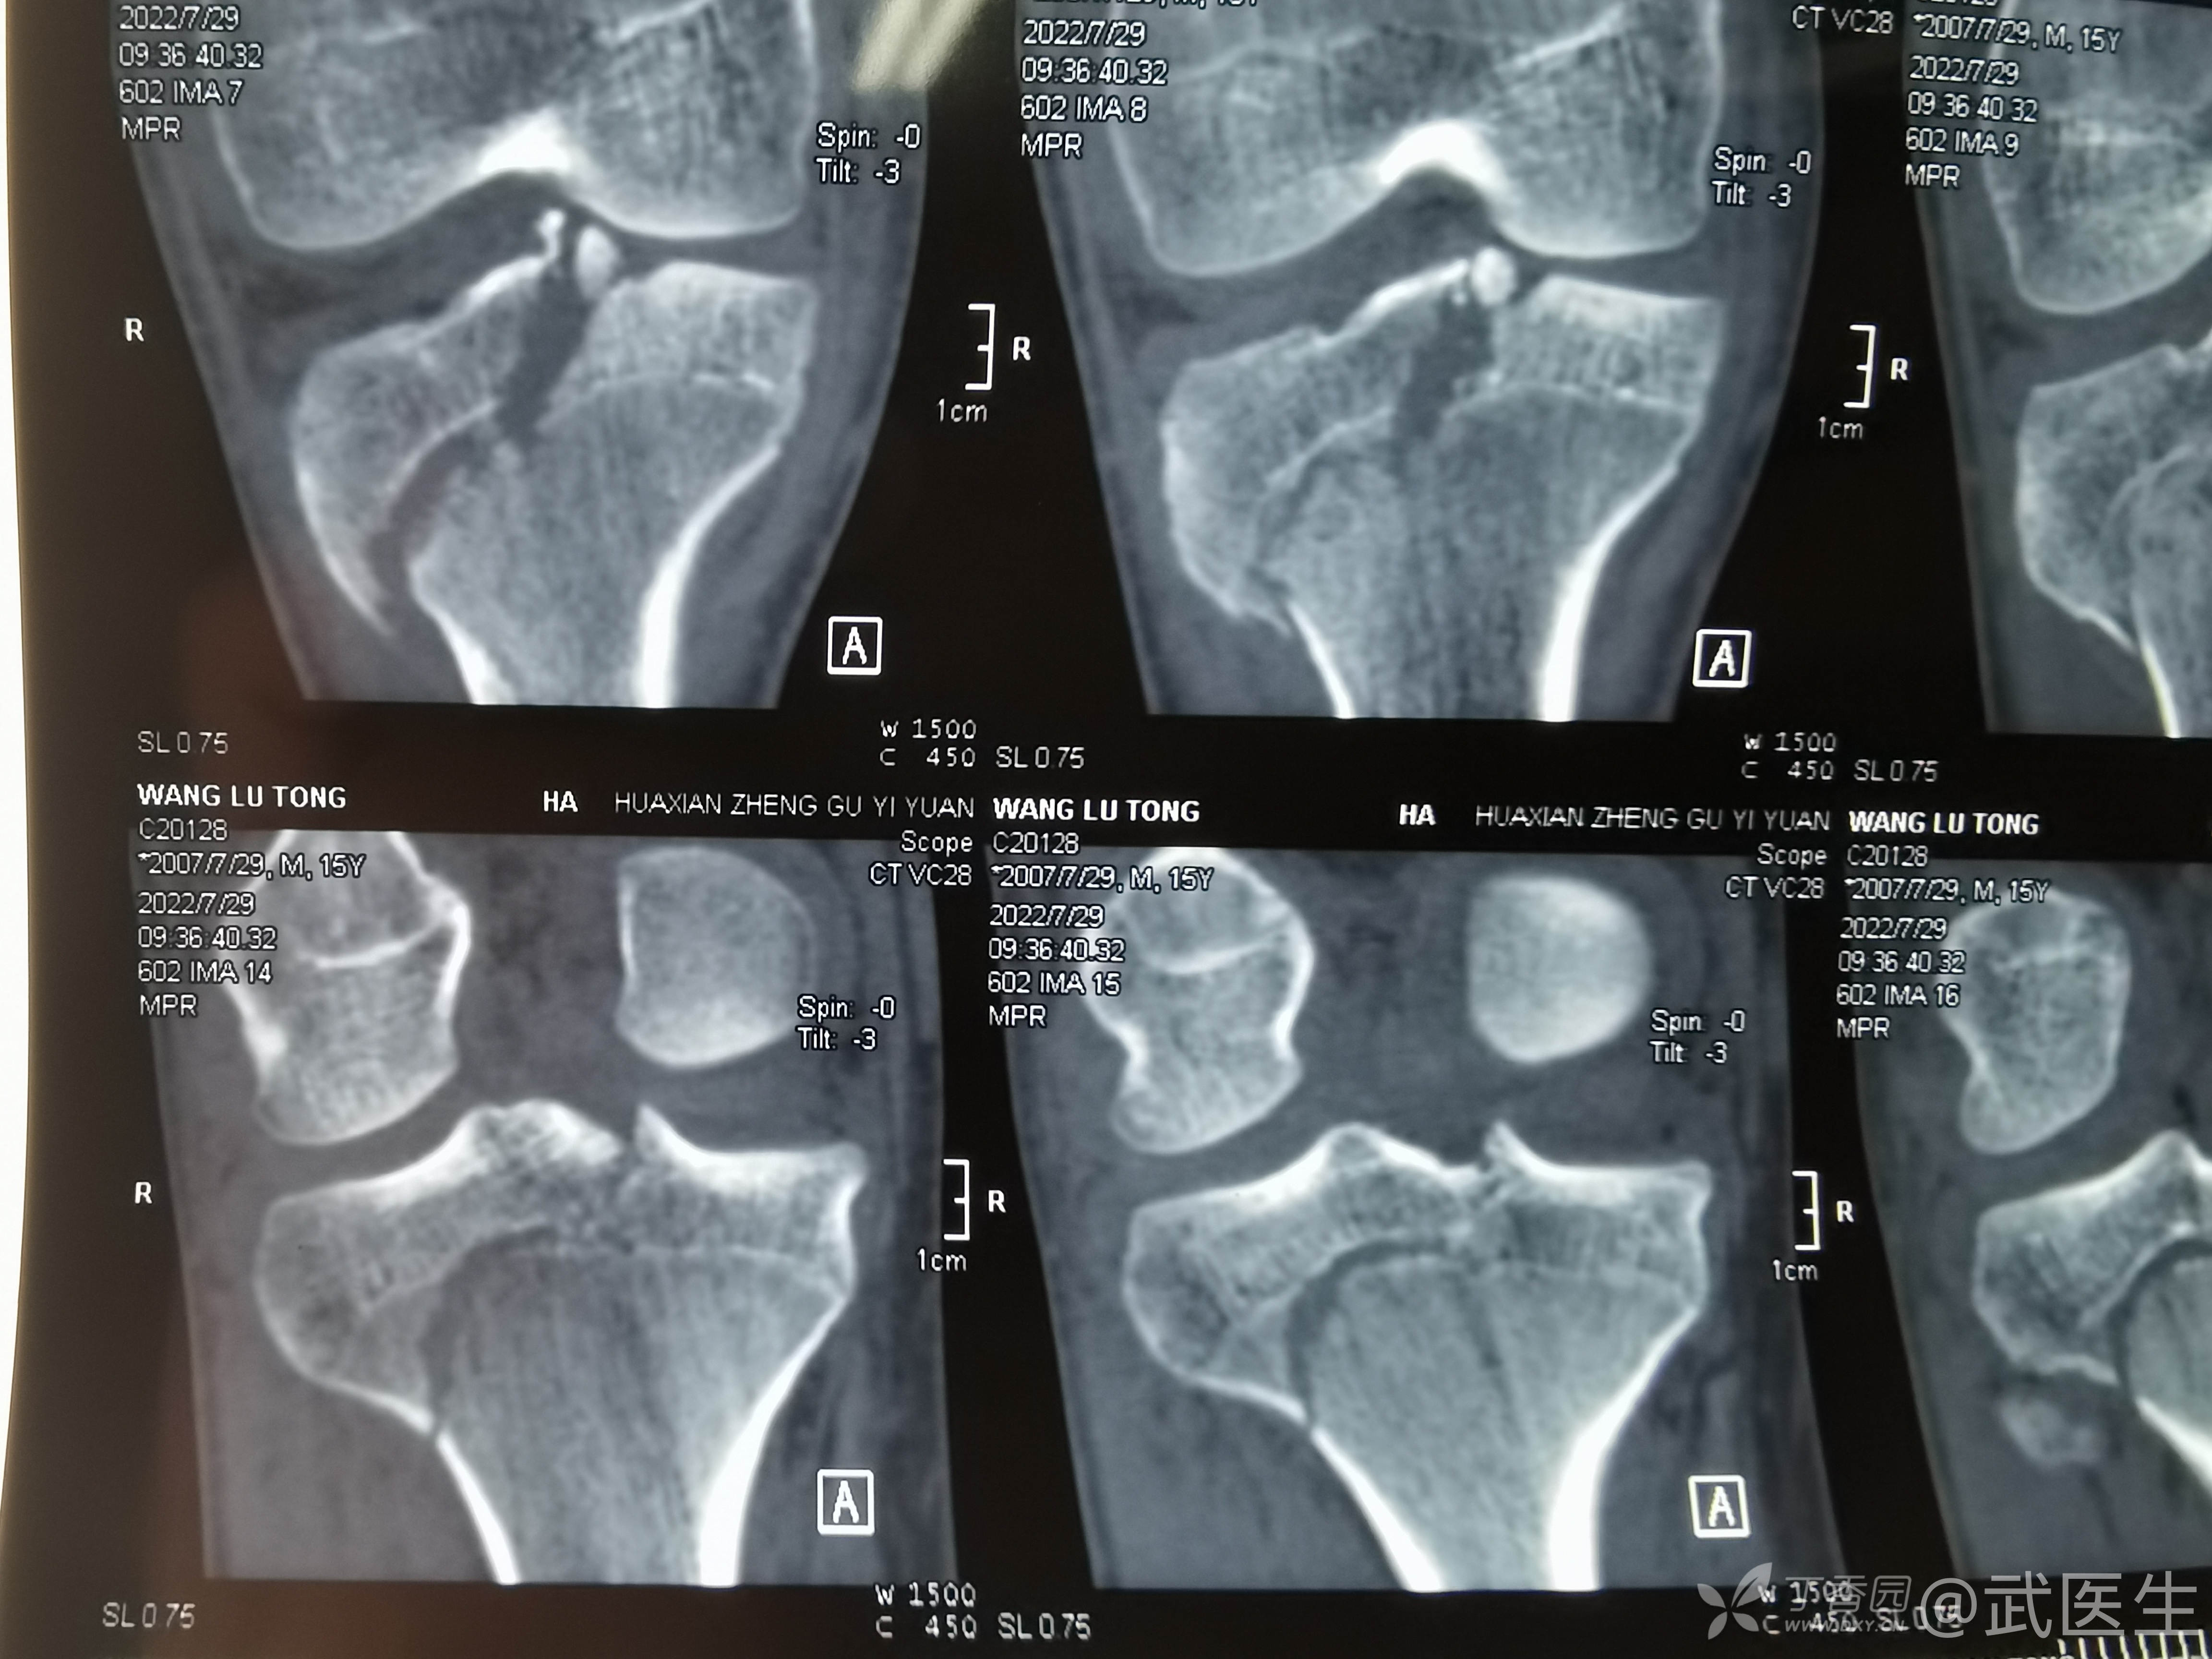

男,15岁,骑摩托车摔伤致右膝疼痛,出血,活动受限三小时就诊,门诊诊断“右胫骨平台骨折,右膝挫裂伤”急诊入院,片子如下,受伤体位照缺失

15岁,骨骺存在,关节加压固定,外侧板支撑